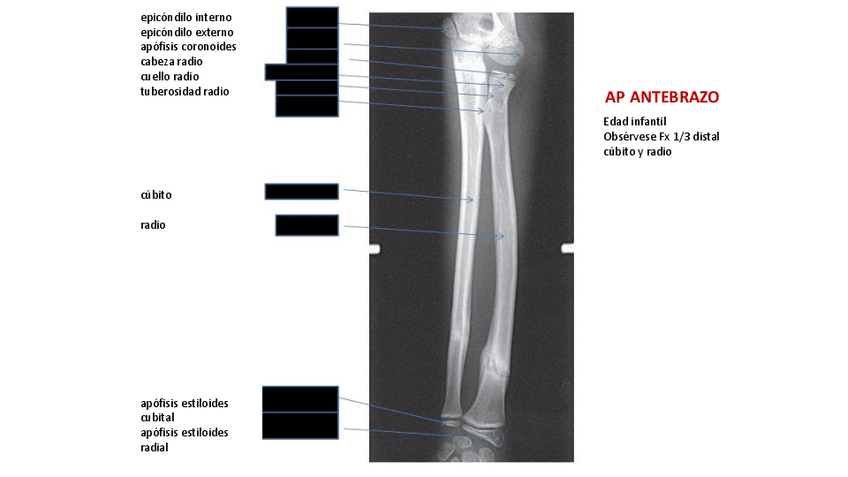

He publicado nuevos apuntes de Técnicas de Radiología Simple: tema-2.Extremidad-superior-y-cintura-escapular.pdf

T3-Miembro-superior.pdf